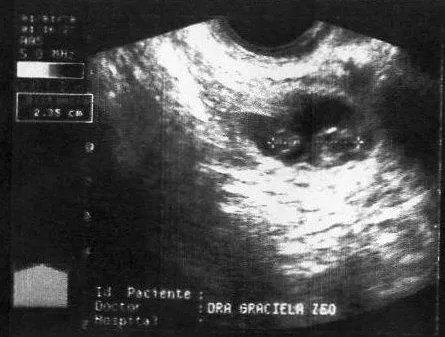

Ecografias recomendadas en el embarazo | Sintomas de Embarazo ...

Indica el motivo para eliminar esta imagen: